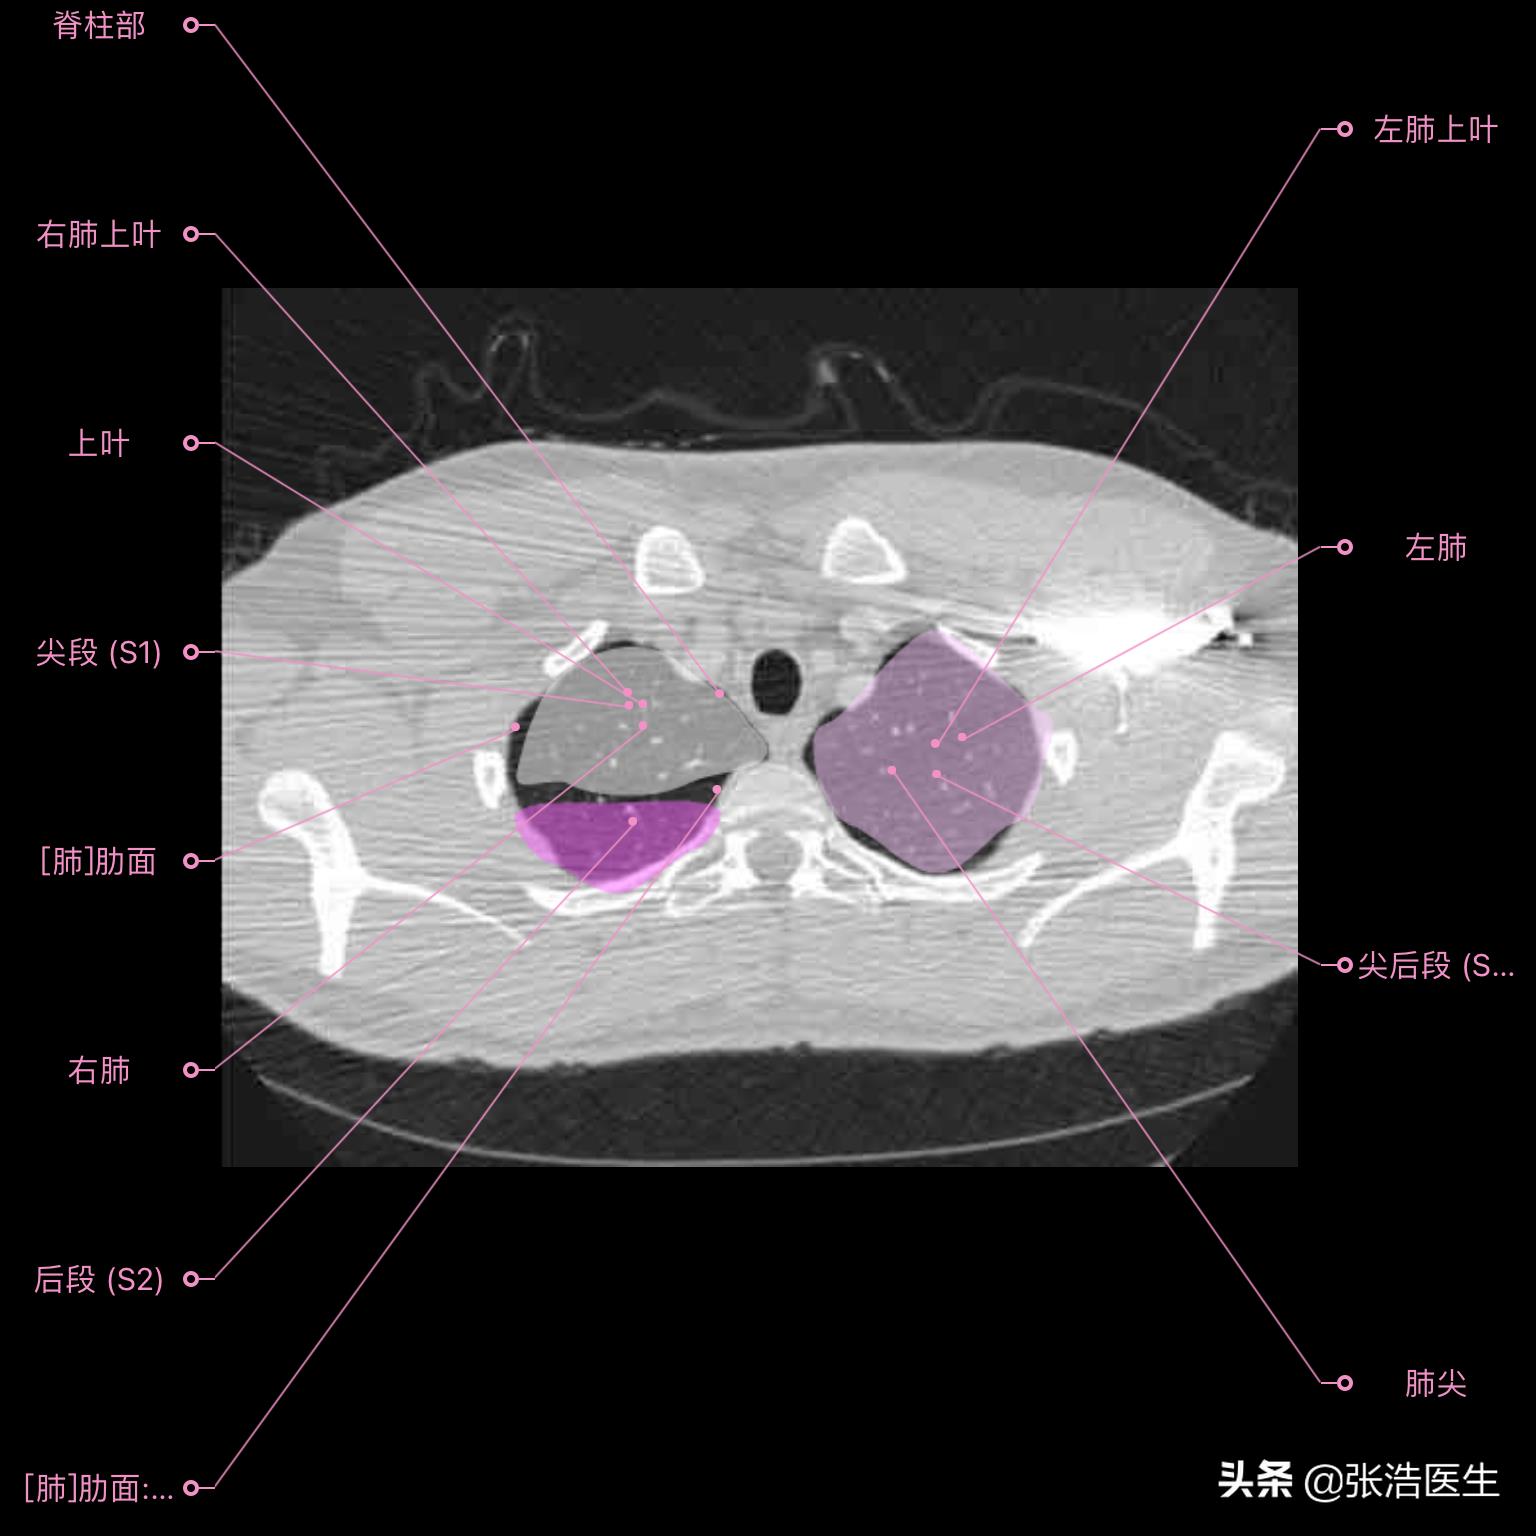

肺部CT横断面高清解剖图谱(图层1)